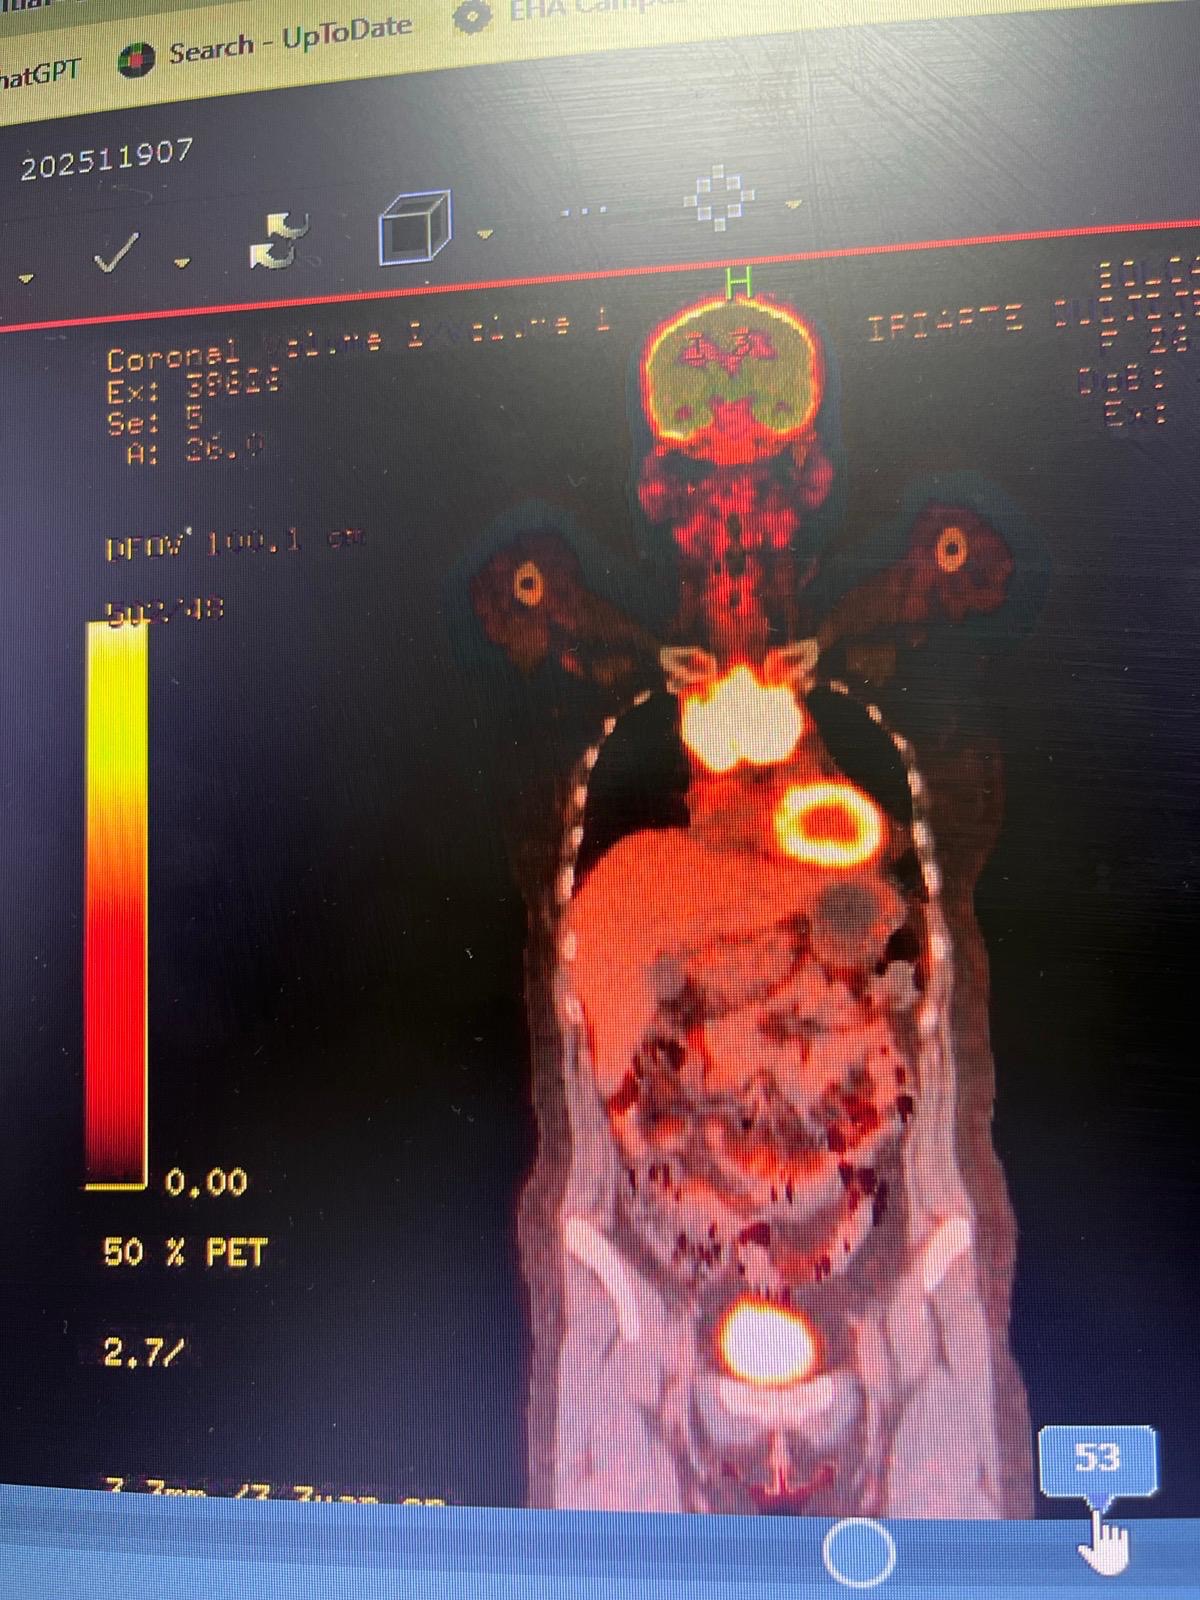

Hace unos meses me detectaron un tumor en el mediastino, después recibí el diagnóstico oficial que me sacudió por completo, linfoma no Hodgkin de células grandes B de alto grado. Desde entonces, he pasado por consultas médicas, exámenes, tratamientos, medicamentos y procedimientos que son indispensables para mi recuperación, pero también muy costosos. A pesar de dar mi mejor esfuerzo, los gastos han ido aumentando y ya no puedo afrontarlos sola.

A few months ago, a tumor was found in my mediastinum. Later, I received the official diagnosis that completely shook my world: high-grade diffuse large B-cell non-Hodgkin lymphoma. Since then, I have gone through medical appointments, tests, treatments, medications, and procedures that are essential for my recovery—but also very expensive. Despite giving my best effort, the costs keep rising, and I can no longer face them on my own.